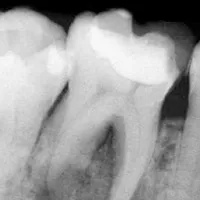

根管治療を成功させるためには、歯の根の構造を正確に把握し清掃することが求められます。 なぜなら、歯の根は人によって異なるためです。根がまっすぐ伸びているものばかりではなく、枝分かれしていたり、意外な角度で曲がっていたり、細すぎたりなど、歯によって個性があります。

上記のように、人によって異なる根の構造を把握するために、多くの歯科医院がレントゲン撮影を試みるのですが、レントゲンでは平面としてしか捉えることができないため、正確な根の構造を知ることは極めて困難だと言えます。 当院が導入している歯科用CTでは、歯の内部を立体的に撮影可能であり、根の構造を正確 に把握することができるため、根管治療の成功に大きく貢献しています。 根の構造を的確に把握することが成功の鍵を握る根管治療では、歯科用CTは必要不可欠だと言っても過言ではありません。

レントゲンで撮影した場合

歯科用CTで撮影した場合